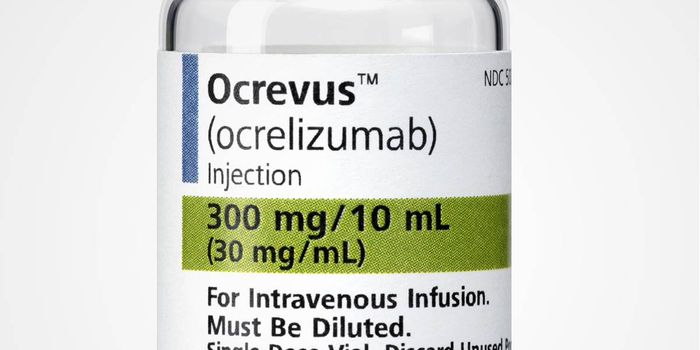

DEC 29, 2016Clinical & Molecular DXA drug that weakens the immune system is showing big promise as potentially the first treatment option for multiple scle ...